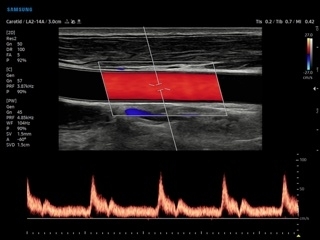

- AutoIMT — автоматическое вычисление комплекса интима-медиа общей сонной артерии (Intima Media Thickness). Данная оценка имеет большое значение для ранней диагностики атеросклероза и оценки риска развития инсульта и инфаркта миокарда;

- 2D Arterial Analysis — программа, позволяющая автоматически провести анализ толщины и эластичности стенок разных участков сонной артерии, с выведением результатов в графической форме в движении (кинопетле) аналогично программе Strain для эхокардиографии;

- Сонные артерии: автоматическая, полуавтоматическая, ручная трассировка доплеровского спектра; ПСС, КДС, %СтПлощ, %Ст Диам, площадь сосуда, диаметр сосуда, средняя толщина интимы, объемный кровоток;